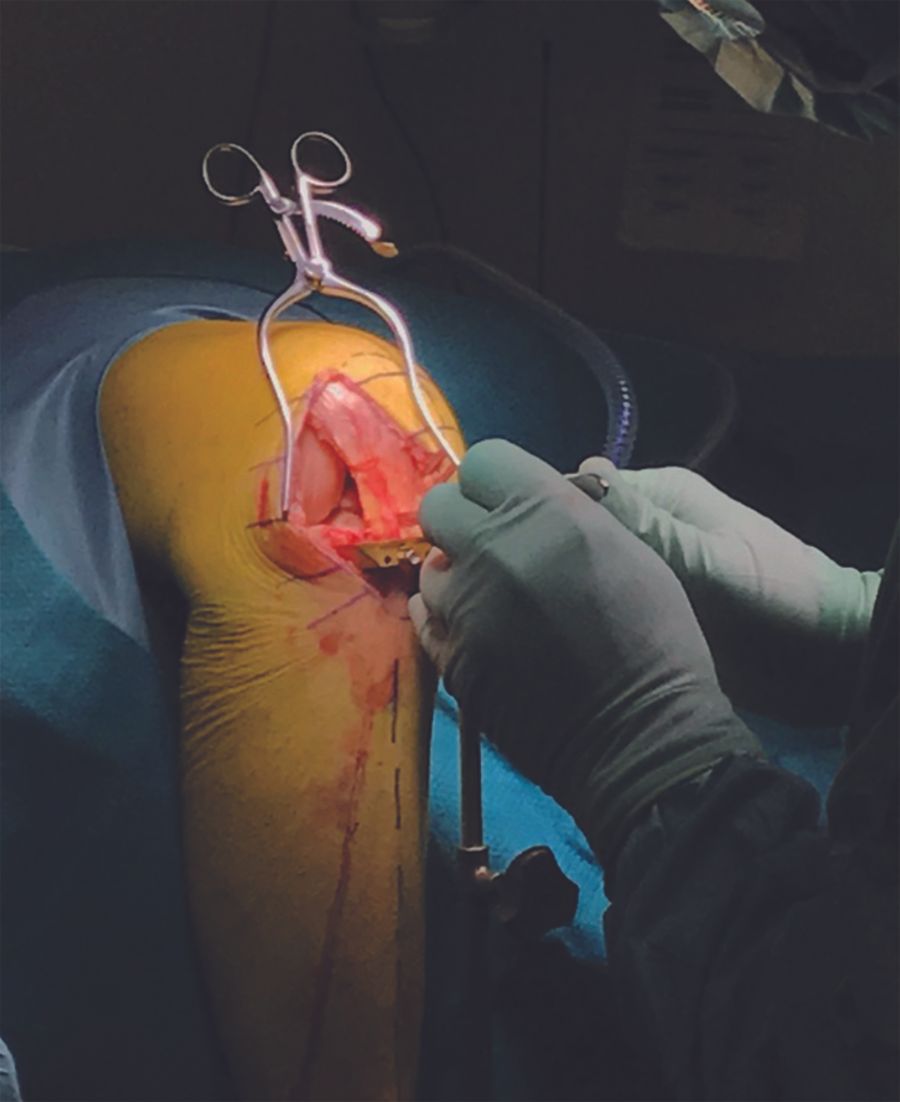

- Incision and joint inspection (figures 3a, 3b)

The skin incision is made from a little below the top of the patella to the level of the tibial tuberosity. The incision is made slightly medial to the lateral margin of the patella and along the lateral border of the patella tendon. This position of the incision helps to facilitate the ease of the partial vertical split of the patellar tendon and the entry of the saw blade for the sagittal tibia cut through the split. The capsular incision is made lateral para-patellar.

The joint is then inspected to secure that the indications to perform LUKA is still fulfilled. Osteophytes are removed from the lateral margin of the lateral condyle and from both sides of the intercondylar notch around the ACL. Any osteophytes anterior to the ACL footprint anterior on the tibia are removed. Any postero medial osteophytes on the lateral condyle are removed to ensure smooth and unforced introduction of the saw blade for the sagittal tibia cut. The front of the tibia is exposed between tibial tuberosity and to Gerdy’s tubercle and the visible part of the lateral meniscus is excised.

* The tibia (figures 4, 5, 6)

An extramedullary guide is placed parallel to the tibia spine (when viewed from the anterior and lateral view). This will facilitate a perpendicular component alignment and a posterior slope aiming for 7 degrees of posterior slope. At the upper end the guide must be placed against the bone and the aim is that the horizontal resection is made 1-2 mm below the most worn part of the tibia. One pin is enough to secure the upper end of the guide. I make the sagittal saw cut first and aim to make the resection just off the lateral, intercondylar tibia spine and with the saw blade pointing towards the anterior superior iliac spine (marked by the assistant) to get proper medial-lateral and rotational orientation of the implant. The sagittal saw cut is made through a splice in the mid substance of the patellar tendon. If the saw blade is introduced from the lateral side of the tendon it may be forced in external rotation. I usually mark the anterior part of the desired sagittal saw cut with the “burning stick”. This will make saw blade positioning easier and more stable. When making the saw cut it must extend to the posterior cortex and the saw must remain parallel to and not below the level of the upper end of the tibia guide. The horizontal cut is made through a slotted shim is placed at the upper end of the tibia guide (replacing the non-slotted shim used for the sagittal saw cut) maintaining the intended 7 degree posterior slope. A retractor should always be in place at the level of the horizontal cut protecting the LCL. The resected specimen is removed. In full extension, using feeler gauges, it is secured that the depth of tibia resection will allow for a size 4 implantation (the smallest possible is a size 3). If not the tibia is recut simply by removing the slotted shim and cutting directly against the upper end of the tibia guide.